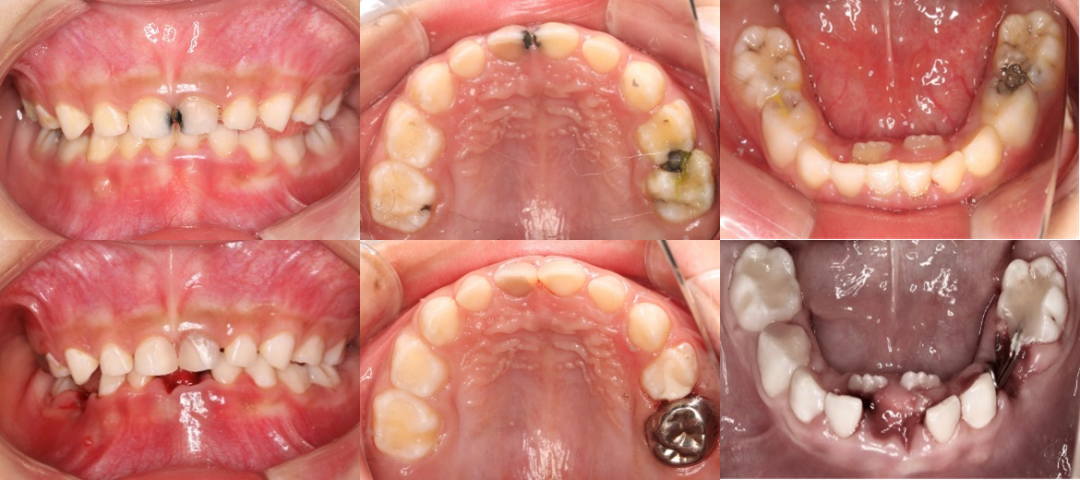

病例一:7岁的孤独症患儿因无法配合常规牙科检查及治疗,目前已经出现牙痛、牙齿松动、进食困难的情况,加上换牙期的到来,儿童常见的新牙已萌,旧牙未脱而出现的“双排牙”(乳牙滞留)更是加剧了家长的担心。

两名患儿均存在多颗乳牙龋坏、牙髓感染甚至残根残冠的问题,因年龄小、配合度低,传统门诊治疗难以完成。口腔科多学科联合治疗小组针对不同的情况为每位患儿制定个性化、系统化的全程诊疗方案。病例一由刘钦捷主治医生、谭晓颖医师和黄芬主管护师全程在橡皮障下2小时就完成了全口口腔问题的处理,包括龋齿充填术、活髓切断术、金属预成冠修复术、滞留乳牙拔除术、即刻固定嵌入式间隙保持器的制备及全口涂氟等。病例二由谭晓颖医师和林慧芬主管护师完成,包括一次性根管治疗、前牙美学微创树脂冠修复、金属预成冠修复、窝沟封闭、残根残冠拔除等治疗。这些在门诊需要孩子与家长请假复诊多次的治疗操作,如今只需2至3小时即可完成。

▲病例一